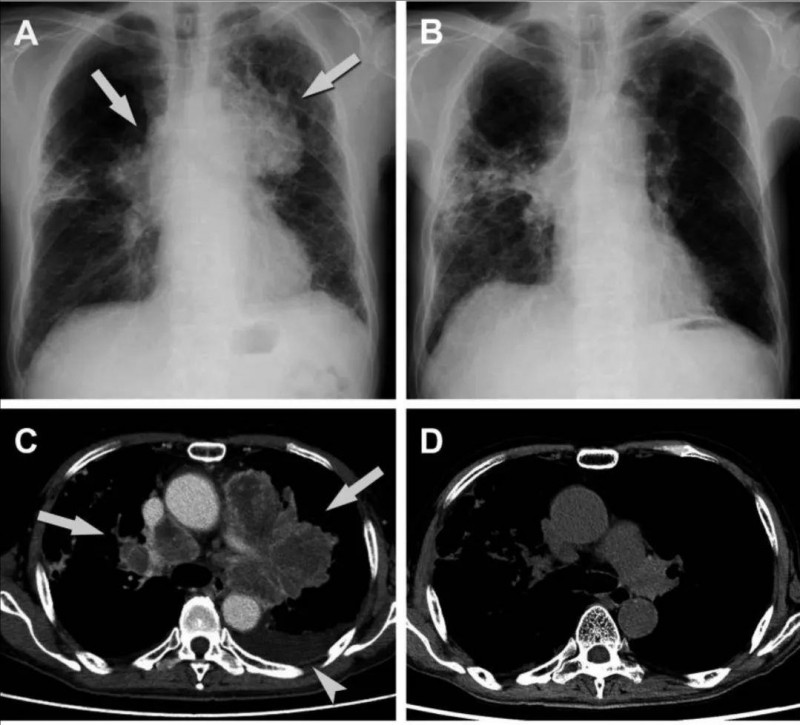

特别值得关注的是一位66岁的男性患者(TU-2844),他患有左上叶原发性肺癌并伴有脑转移,同时还出现了肺炎症状。通过支气管肺活检,结果显示为腺癌;然而在进行脑转移切除术之后,病理诊断却为大细胞神经内分泌癌。尽管对其实施了全脑照射以及CDDP+VP-16全身化疗方案,但患者的病情仍在持续进展。鉴于该患者有间质性肺炎病史,医生为其采用TS-1进行二线化疗,可最终因患者出现腹泻症状而被迫停止。于是,该患者入组接受Vγ9Vδ2T细胞治疗。

在第一次注射Vγ9Vδ2T细胞的5天后,患者出现了低烧、轻微咳嗽以及呼吸困难的症状。CT检查显示出间质性肺炎加重的迹象;对此,医疗团队立即给予患者全身性类固醇和抗生素治疗,患者随后很快康复。在第一次治疗的5周后,患者接受了第二次Vγ9Vδ2T细胞治疗,3天后,发热、咳嗽、呼吸困难等症状再次出现,再次给予全身激素及抗生素治疗,患者症状得以好转。令人惊喜的是,在整个治疗期间,患者肺部肿瘤及淋巴结肿大情况明显缩小(详见下图)。

▲图源“J Immunother Cancer”,版权归原作者所有,如无意中侵犯了知识产权,请联系我们删除